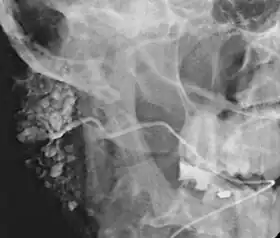

![]() Sialogram in a patient suspected of Sjögren's syndrome | |

This procedure is indicated when there is recurrent swelling and pain on the face but ultrasound has not revealed any problems. If Sjögren syndrome (also known as Sicca syndrome, an autoimmune disease that affects the lacrimal and salivary glands, causing reduced tears and saliva production) is suspected, this procedure is useful. Besides, when interventional proecudre is planned such as stone removal from salivary ducts or dilatation of the strictures in the salivary gland, this procedure is also indicated.[4] However, for those who are pregnant, with allergy to iodinated contrast, and ongoing infection or inflammation of the face, the procedure is contraindicated.[4]

This study is interpreted by evaluating the morphology of the salivary ducts for obstructions and chronic inflammation. Sialodochitis is a term describing dilation of the ducts caused by repeated inflammatory or infective processes. There is also irregular salivary duct stricture (narrowing) of the duct, which creates an appearance known as "sausage link" pattern on a sialogram. Suggestions of abscesses and autoimmune diseases such as Sjögren syndrome can also be elicited. Sialadenitis is inflammation of the salivary glands, which may cause acinar atrophy and create an appearance known as "pruning of the tree" on a sialogram, where there are less branches visible from the duct system. A space occupying lesion that occurs within or adjacent to a salivary gland can displace the normal anatomy of the gland. This may create an appearance known as "ball in hand" on an sialogram, where the ducts are curved around the mass of the lesion.[6]